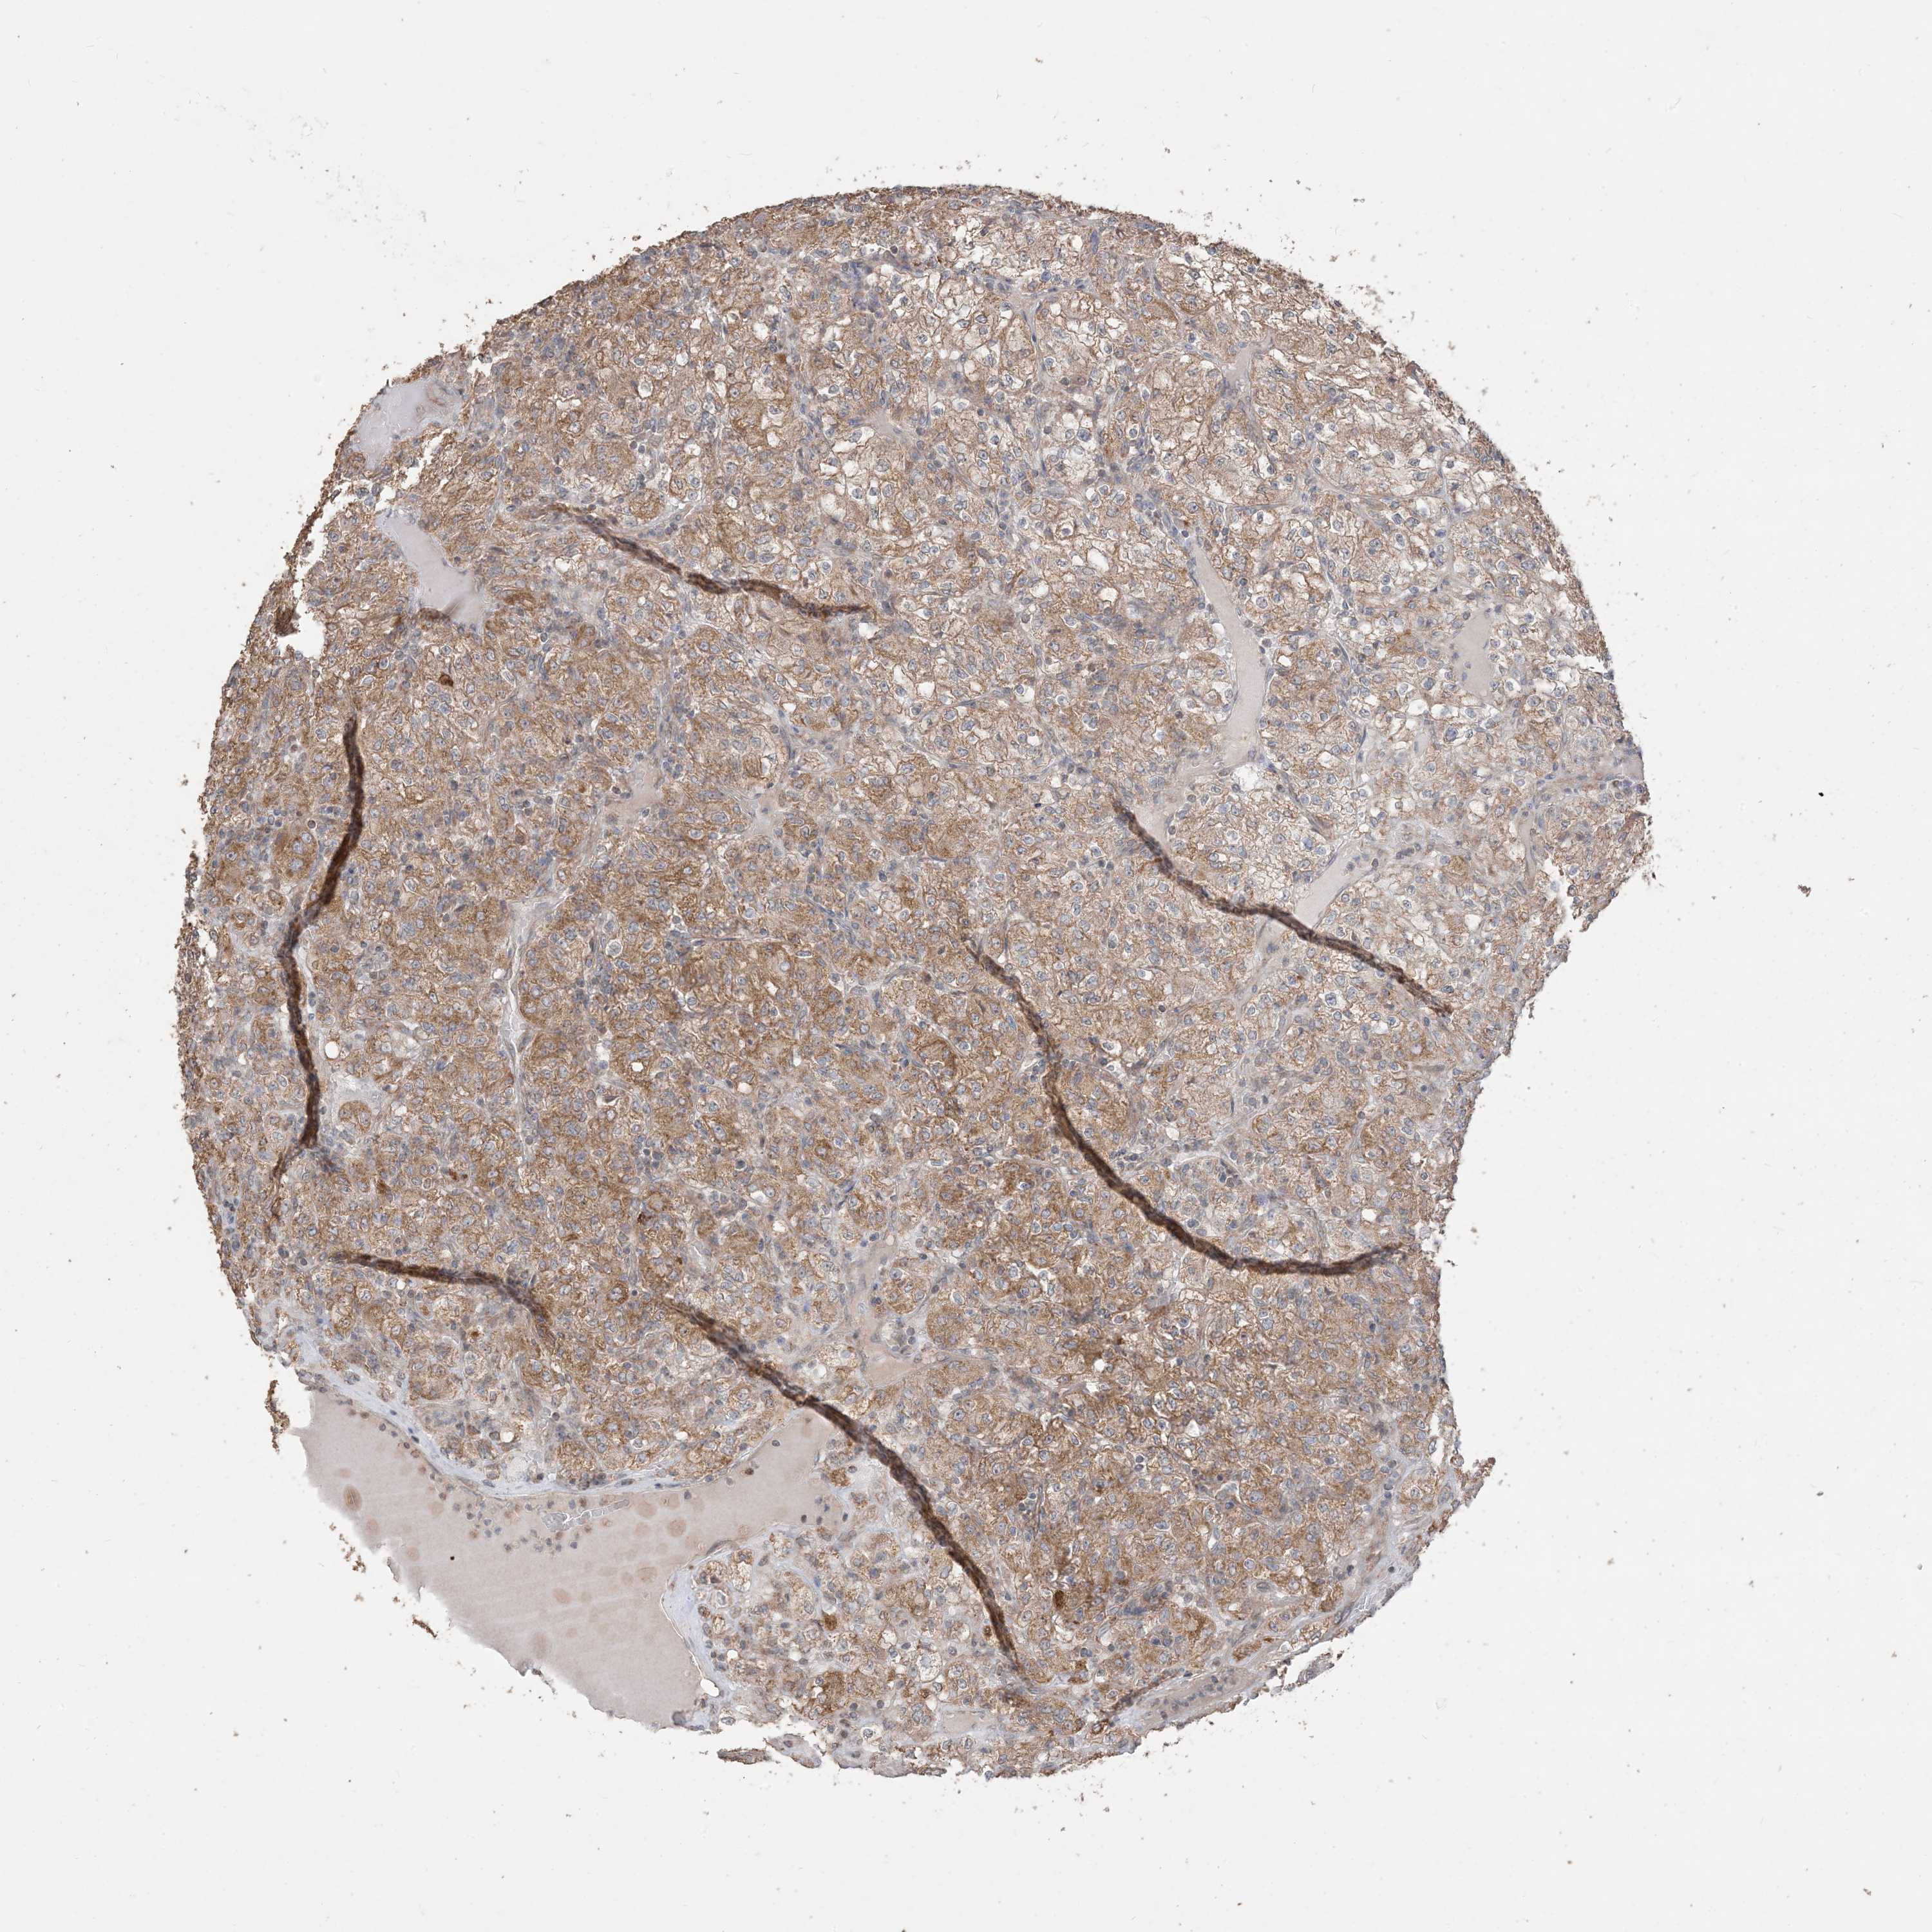

KIDNEY RENAL CLEAR CELL CARCINOMA (TCGA) - Interactive survival scatter ploti

The Survival Scatter plot shows the clinical status (i.e. dead or alive) for all individuals in the patient cohort, based on the same data that underlies the corresponding Kaplan-Meier plots. Patients that are alive at last time for follow-up are shown in blue and patients who have died during the study are shown in red.

The x-axis shows the expression levels (FPKM) of the investigated gene in the tumor tissue at the time of diagnosis. The y-axis shows the follow-up time after diagnosis (years). Both axes are complimented with kernel density curves demonstrating the data density over the axes. The top density plot shows the expression levels (FPKM) distribution among dead (red) and alive patients (blue). The right density plot shows the data density of the survived years of dead patients with high and low expression levels respectively, stratified using the cutoff indicated by the vertical dashed line through the Survival Scatter plot. This cutoff is automatically defined based on the FPKM cutoff that minimizes the p-score. The cutoff can be changed by dragging the vertical line or by entering a cutoff value in the square labeled "Current cut-off".

Under the Survival Scatter plot the p-score landscape (black curve; left axis) is shown together with dead median separation (red curve; right axis). Dead median separation is the difference in median mRNA expression between patients who have died with high and low expression, respectively. It is calculated as follows: median FPKM expression of dead patients with high expression - median FPKM expression of dead patients with low expression. This is intended to aid the user in visually exploring custom cutoffs and the associated p-scores and dead median separation.

Individual patient data is displayed and can be filtered by clicking on one or more of the category buttons on the top of the page. Categories describing expression level and patient information include: high, low, alive, dead, female, male and tumor stages. The scale of the x-axis can be toggled between linear and log-scale by clicking on the "x log" button. Mouse-over function shows TCGA ID, patient information and mRNA expression (FPKM) for each patient.

& Survival analysisi

Kaplan-Meier plots summarize results from analysis of correlation between mRNA expression level and patient survival. Patients were divided based on level of expression into one of the two groups "low" (under cut off) or "high" (over cut off). X-axis shows time for survival (years) and y-axis shows the probability of survival, where 1.0 corresponds to 100 percent.

SIRT3 is not prognostic in Kidney Renal Clear Cell Carcinoma (TCGA)

: 12.71

Average pTPM 14.0

Number of samples 521